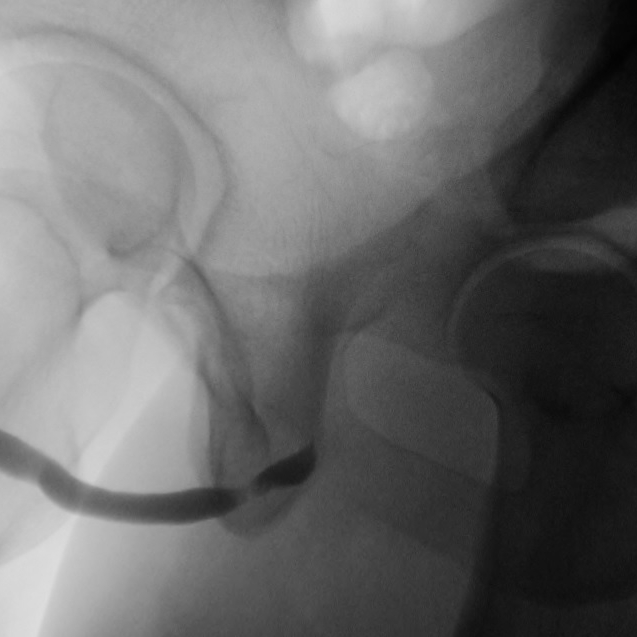

Retrograde Urethrogram / Voiding Cystourethrogram. A retrograde urethrogram (RUG) and Voiding cystourethrogram (VCUG) are two X-ray studies that provide valuable information to determine the length and location of your urethral stricture. A RUG is performed by injecting a contrast material backward into the urethra. The RUG provides great information on the anterior urethra, however provides very little information on the posterior urethra. A VCUG is performed first by passing a small catheter past your scar and into the bladder. The bladder is then filled with more contrast material. The catheter is then removed and X-rays are taken while you begin to start urinating. The VCUG provides valuable information on the posterior urethra.

The follow-up after urethroplasty is very important because most urethral strictures recur within the first year or two after surgery. Prior to when you return to the clinic, the bladder is filled with x-ray contrast and the catheter that was placed during surgery is gently removed. While X-rays are being taken, the patient voids and the area of the surgery is evaluated. If the area of surgery is healed, the catheter is left out and patients begin to void normally. This is typically done at 3-4 weeks after surgery. Ideally, within the same day, Dr. Osterberg will also arrange your first postoperative visit.